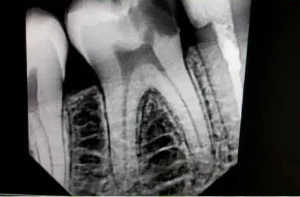

| 1 |

| Digital X-ray | We use a high-resolution dental X-ray to precisely locate the infected tooth area before starting the root canal treatment at Bright Smile Dental clinic Faisalabad. |